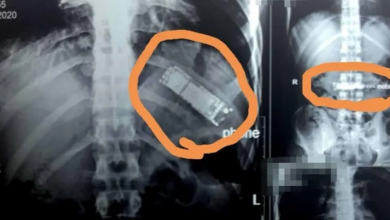

حادثة ولا في الخيال.. هاتف في معدة شاب مصري لـ7 أشهر!